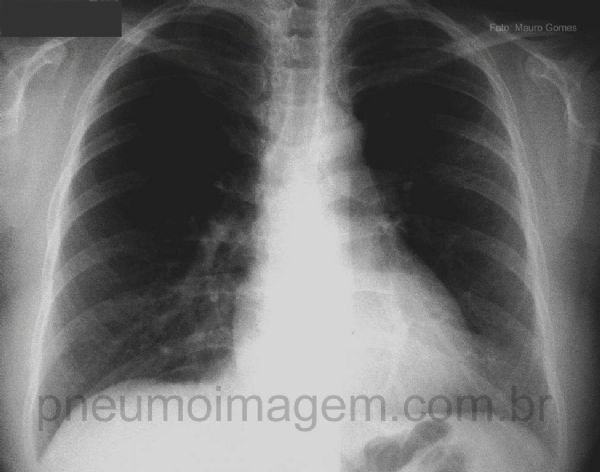

A lesão, neste caso, é arredondada e localiza-se no lobo inferior esquerdo. Acredita-se que este formato seja devido à disseminação da infecção através dos poros de Kohn e canais de Lambert, ou por destruição das paredes alveolares. Broncogramas aéreos no seu interior não é a rotina (17% dos casos). O diagnóstico diferencial é feito principalmente com o carcinoma broncogênico.

The injury in this case is located in the left lower lobe. It is believed that this format is due to the infection spreading through the pores of Kohn and the channels Lambert, or by destruction of alveolar walls. Air bronchograms inside is not routine (17% of cases). The differential diagnosis is made primarily with bronchogenic carcinoma.